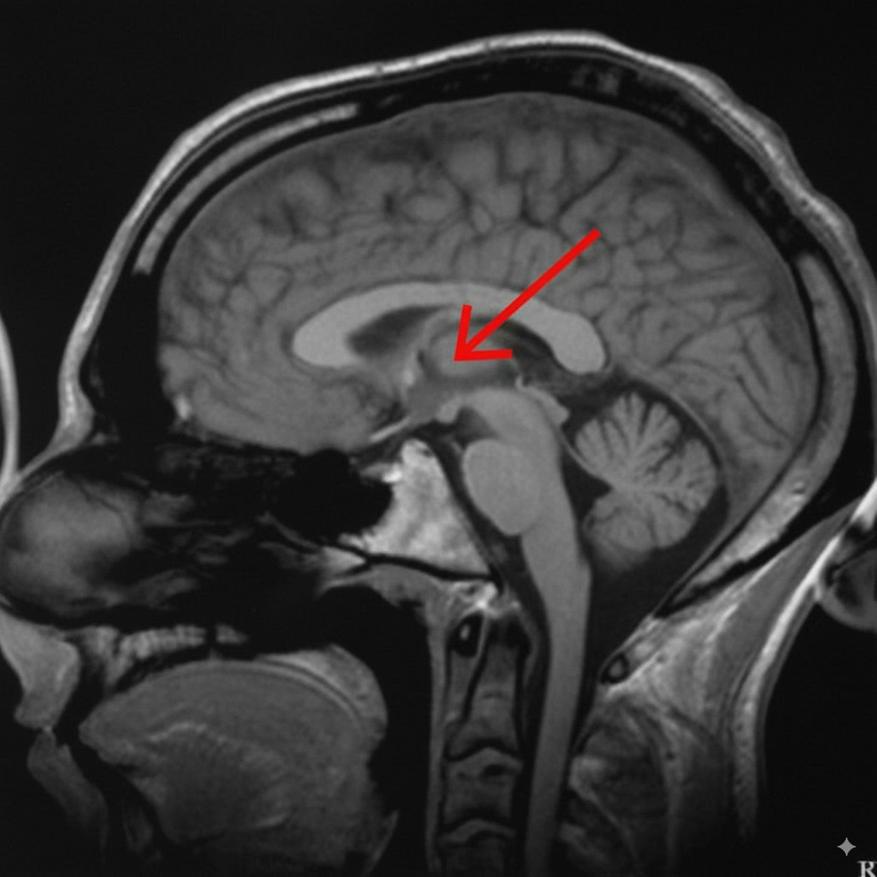

Таламус человека на МРТ-снимке, отмечен стрелкойАвтор: Brian_chrischan CC BY-SA 3.0 Источник: commons.wikimedia.org